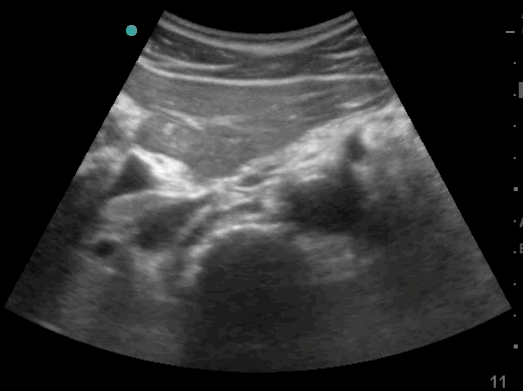

23_Abdomen_Pelvic_Sagittal

Free fluid is seen between the bowels, above the bladder